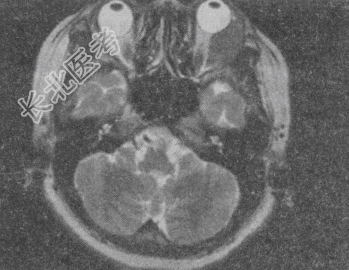

- 单项选择题女,52岁, 左眼球突出20余年,T

均正常, 影像检查如图所示,最可能的诊断是